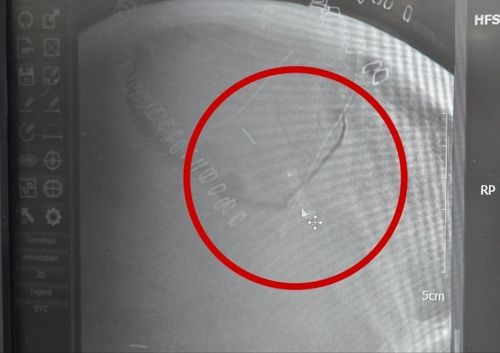

톱날이 박힌 머리뼈 톱날이 박힌 머리뼈

동그라미 부근의 머리뼈에 쇠톱 날이 박혀 자기공명영상(MRI)이 제대로 찍히지 않았다. MRI는 자기공명을 이용하는데 금속 물질이 있어 정상적으로 작동하지 않았다고 한다. [B씨 제공]